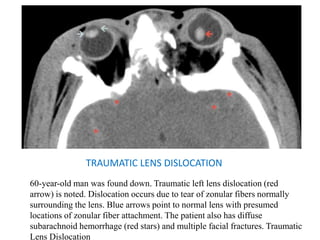

TRAUMATIC LENS DISLOCATION

60-year-old man was found down. Traumatic left lens dislocation (red

arrow) is noted. Dislocation occurs due to tear of zonular fibers normally

surrounding the lens. Blue arrows point to normal lens with presumed

locations of zonular fiber attachment. The patient also has diffuse

subarachnoid hemorrhage (red stars) and multiple facial fractures. Traumatic

Lens Dislocation